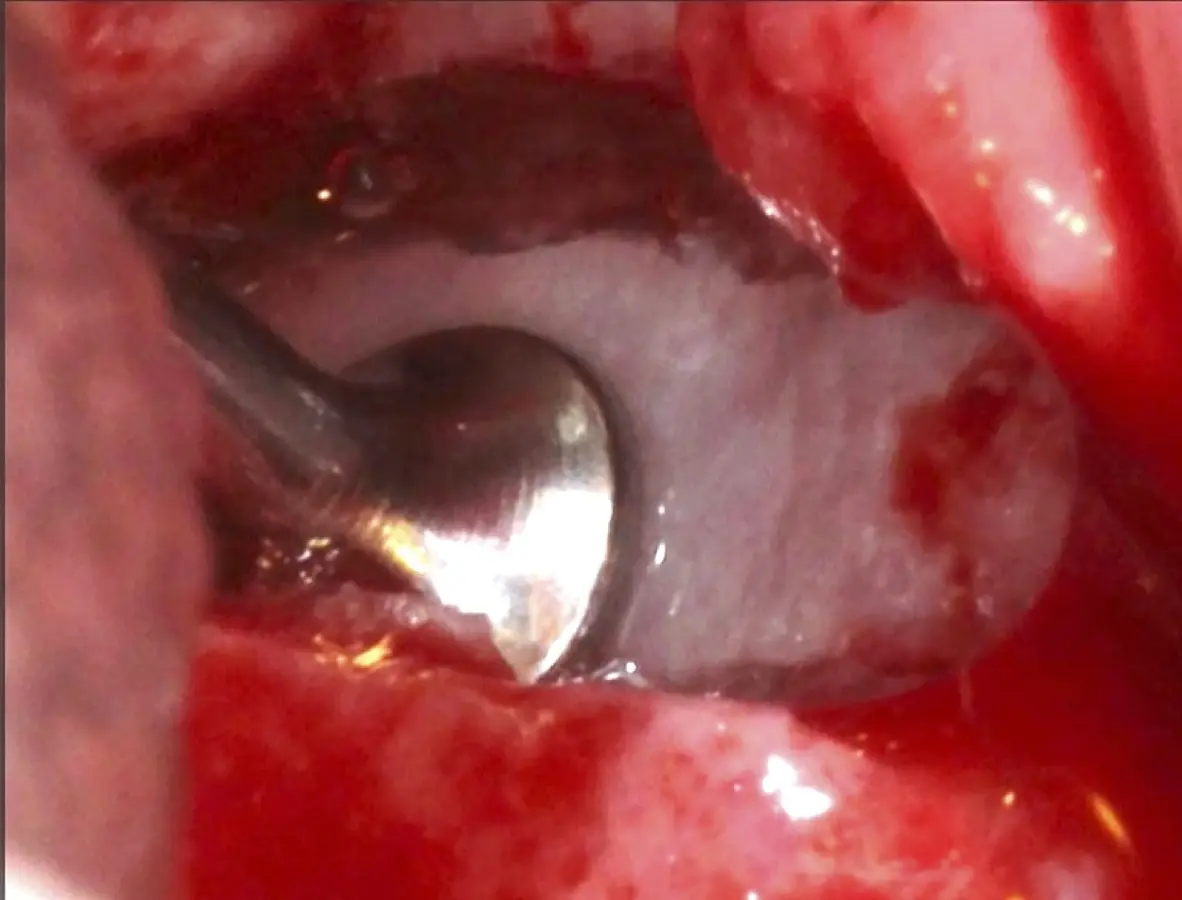

Se inicia la elevación de la membrana de Schneider con el inserto redondeado no cortante en forma de disco, empleando movimientos suaves. El levantamiento puede complementarse con elevadores convencionales, siguiendo la dirección mesiodistal. La fase de desprendimiento inicia con el piso y sigue hacia la pared mesial para terminar, y de ser necesario, hacia la pared posterior. Existen diversos insertos con angulaciones y longitudes para mayor accesibilidad16 (Figura 1).

El tipo de inserto a ser utilizado dependerá del espesor de la pared ósea. Si la pared es menor a 0.5 mm, es mejor utilizar insertos de desgaste para prevenir la ruptura de la membrana de Schneider; si el espesor es mayor a 0.5 mm, se puede utilizar insertos de corte de espesor medio (Figura 3).